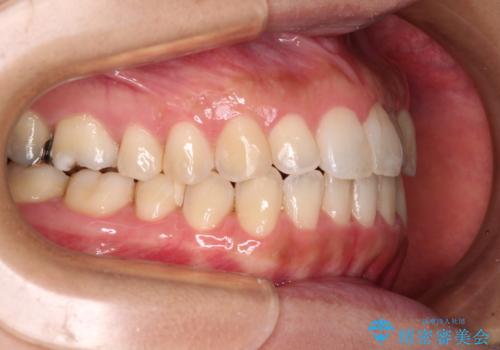

- 前歯の捻れを気にして来院された患者様です。

上顎前歯が捻れて前方に飛び出しており、下顎前歯もそれに沿うようにデコボコとなっていました。

IPR(歯と歯の間を削る処置)によりスペースを獲得して上下前歯のデコボコを改善し、インビザラインにて矯正治療を行うこととしました。